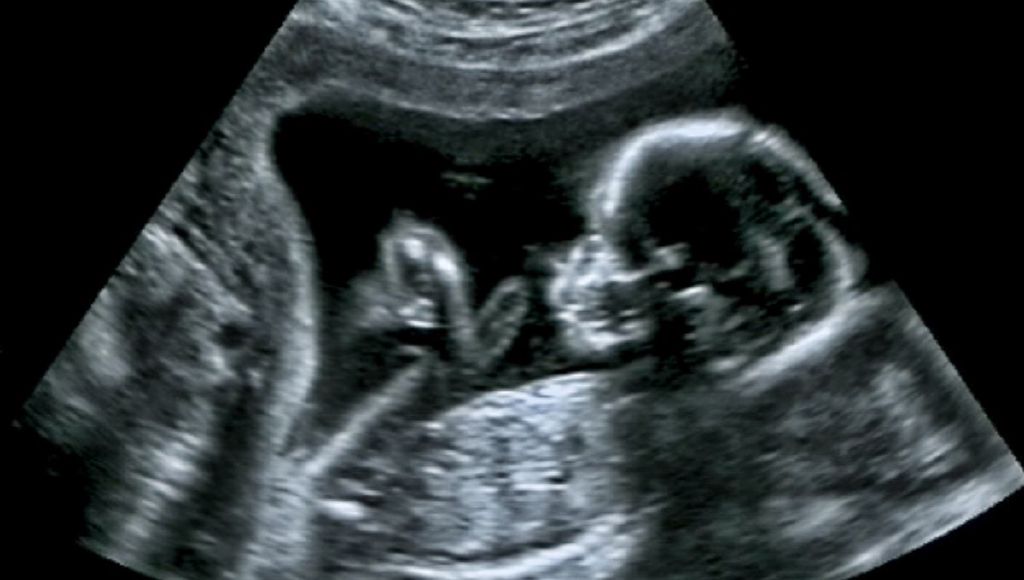

First-Ever Brain Surgery Within The Womb Successfully Treats Deadly Fetal Disorder

The team did the surgery at just 34 weeks.